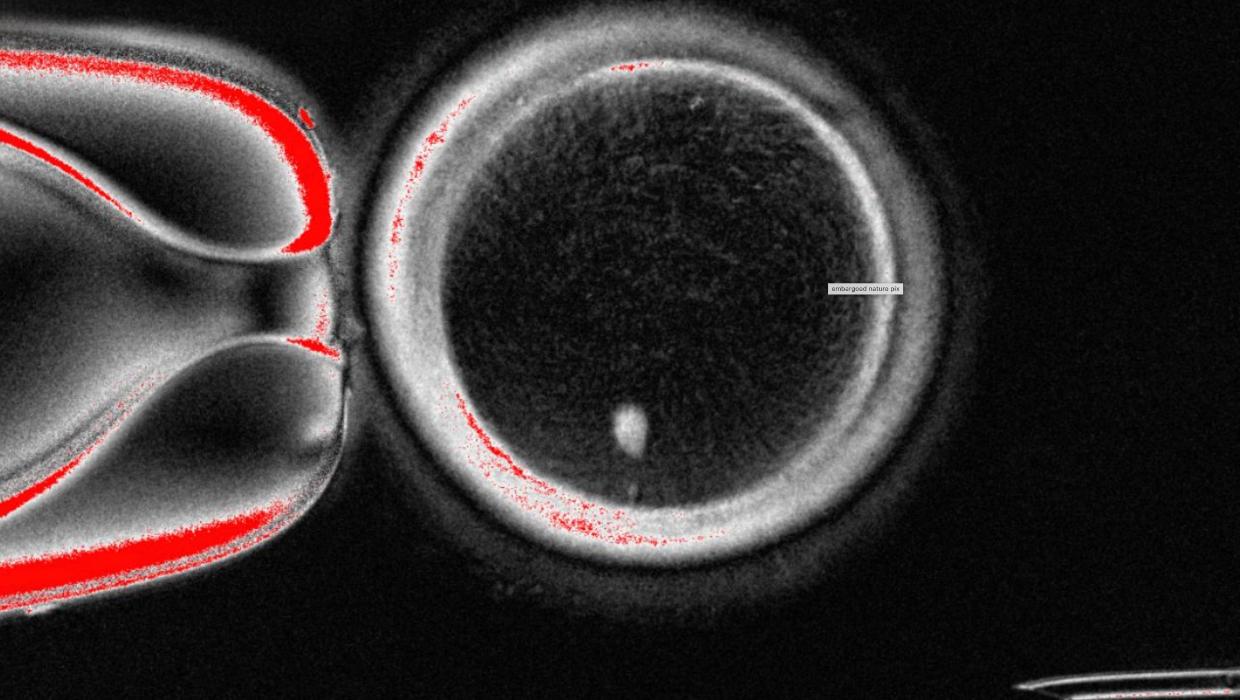

A team of scientists in the United States has successfully transformed human skin cells into fertilizable eggs, marking a significant advancement in reproductive medicine. This breakthrough could pave the way for the development of lab-grown eggs and sperm, potentially helping individuals and couples facing infertility to conceive.

The research, published in the Journal of Cell Biology, showcases the innovative techniques employed by the researchers to coax skin cells into becoming functional gametes. By reprogramming these cells, the scientists aimed to create viable human eggs that could undergo fertilization and support early embryonic development.

The process involved a meticulous series of steps, including the introduction of specific factors that guide skin cells into a pluripotent state, allowing them to develop into various cell types. The researchers then directed these pluripotent cells to differentiate into egg precursor cells, ultimately leading to the formation of fertilizable eggs.